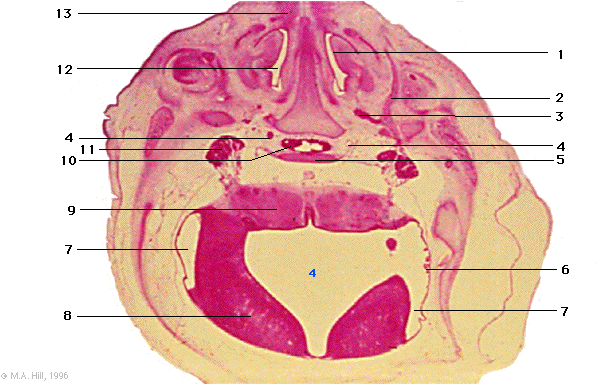

1 |

inferior nasal concha |

2 |

maxillary division trigeminal nerve |

3 |

pterygopalatine ganglion |

4 |

internal carotid artery |

5 |

sphenoid cartilage |

6 |

choroid plexus |

7 |

lateral recess of 4th ventricle |

8 |

cerebellum |

9 |

metencephalon (pons) |

10 |

adenohypophysis |

11 |

trigeminal ganglion |

12 |

nasal cavity |

13 |

nasal plugs |